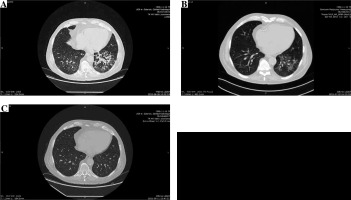

He initially received amoxicillin/clavulanic acid. Bacterial cultures of blood and urine were negative. The symptoms improved, and fever resolved, with a decrease in both WBC and CRP levels over the next few days with empiric antibiotic treatment. There was clinical improvement, but without a radiological resolution. An HRCT scan (Fig. 1A) revealed a disseminated nodular pattern in both lungs, accompanied by peribronchial consolidations and lung parenchyma retraction dominating in the lower lobes. No pleural effusion was seen. Bronchoscopy was unremarkable. A transbronchial biopsy revealed mild nonspecific inflammation with areas of fibrosis in the bronchial walls. Bronchoalveolar lavage was sent for cell count, bacterial and viral culture, and fungal and acid-fast bacillus analysis. Both sputum and bronchoalveolar lavage cultures were positive for Achromobacter denitrificans. After a complete diagnostic workup including repeated bacterial and mycobacterial cultures, QuantiFERON1-TB Gold test, blood CMV-PCR, blood Aspergillus galactomannan and Candida mannan, immunofluorescent staining of bronchoalveolar fluid for Pneumocystis jiroveci, other pulmonary opportunistic infections were ruled out, and a diagnosis of A. denitrificans pneumonia and EVR pulmonary toxicity was made. A 17-day course of piperacillin/tazobactam chosen according to the susceptibility profile (Table 2), and a reduction of the EVR dose to the target trough levels of 2.8-3.2 ng/ml resulted only in partial resolution of radiological abnormalities confirmed by HRCT (Fig. 1B). After three weeks of antibiotic treatment EVR was withheld. EVR discontinuation with no additional antibiotic treatment resulted in complete recovery and a complete resolution of pulmonary infiltrates in an HRCT performed at a further 10-week follow-up (Fig. 1C). The immunosuppressive regimen on discharge was restricted to cyclosporine and glucocorticosteroids.

Fig. 1

A) Initial computed tomography (CT) of the lungs shows poorly defined bilateral patchy consolidations without pleural effusion, B) chest CT after 3-week antibiotic treatment and everolimus (EVR) dose reduction shows only partial resolution of bilateral patchy consolidations, C) CT performed 10 weeks after EVR discontinuation shows complete resolution of symptoms